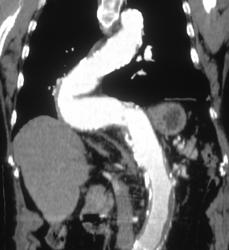

Diagnosis

Endovascular Stent